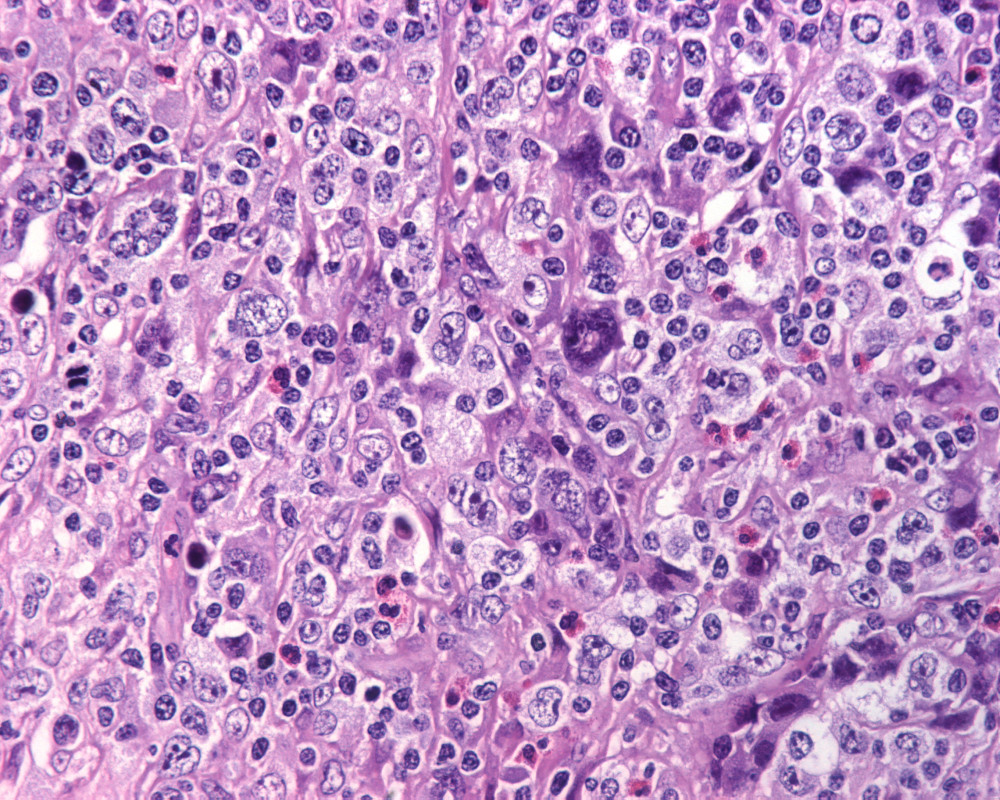

Biopsia de ganglio linfático.

-¿Cuál es su diagnóstico de trabajo por morfología y su diferencial?

DIAGNÓSTICO: LINFOMA DE HODGKIN CLASICO, ESCLEROSIS NODULAR, VARIANTE SINCICIAL